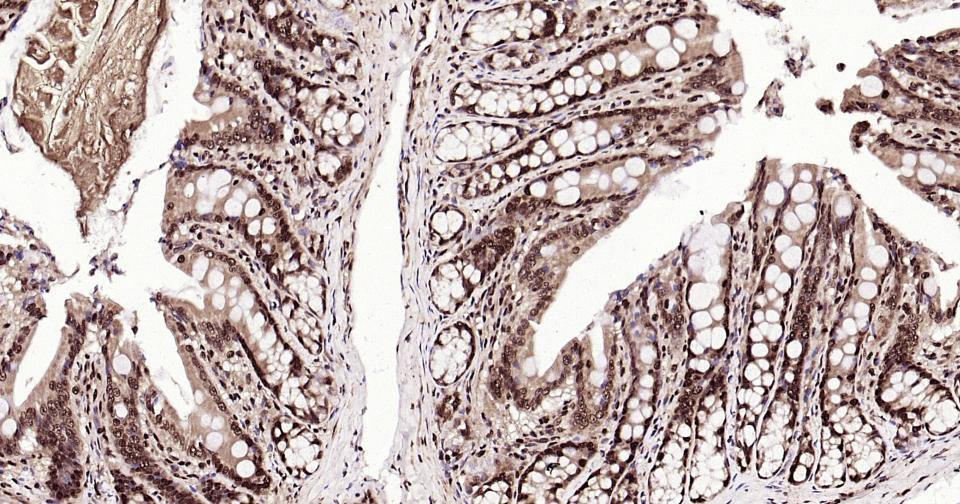

Paraformaldehyde-fixed, paraffin embedded Human Colon; Antigen retrieval by boiling in sodium citrate buffer (pH6.0) for 15 min; Antibody incubation with K27-linkage specific ubiquitin Monoclonal Antibody, Unconjugated(bsm-63007R) at 1:200 overnight at 4°C, followed by conjugation to the bs-0295G-HRP and DAB (C-0010) staining and DAB (C-0010) staining.